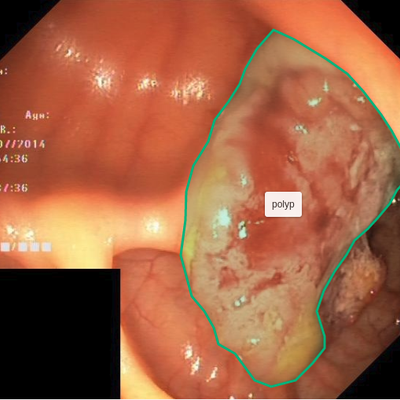

The goal of image segmentation is to assign a label to each pixel of the image so the pixels with the same label share specific characteristics, e.g., the pixels covered by the outline in the Figure 1 show a polyp. Manual segmentation by physicians is still the gold standard for most of the medical imaging modalities, for example, Magnetic Resonance Imaging for evaluating hippocampal atrophy in Alzheimer’s Disease [5] and tumor segmentation of glioma [27]. However, manual image segmentation is tedious, time-consuming, and subject to physician’s bias and inter-observer variation. Therefore, there is a need for an automated and efficient image segmentation technique.

Figure 1 shows example frames from the kvasir dataset where we have additionally marked the polyp tissue with green outline. After annotation, we exported the files to generate masks for each annotation. The exported JSON file contained all the information about the image and the coordinate points for generating the mask. To create a mask, we used ROI coordinates to draw contours on an empty black image and fill the contours with white color. The generated masks are a 1-bit color depth images with white foreground and black background. Figure 2 shows example images, their corresponding segmentation masks and bounding boxes from the Kvasir-SEG dataset.